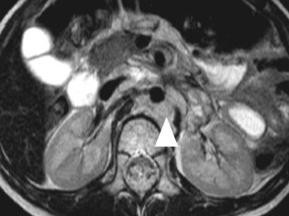

Atezolizumab kann die Zweit- und Drittlinientherapie mit Cabozantinib bei metastasiertem Nierenzellkarzinom nicht verbessern – Gesamtüberleben und PFS werden nicht verlängert, dafür treten häufiger schwere Nebenwirkungen auf, so die Resultate der Studie CONTACT-03.

Bildnachweise